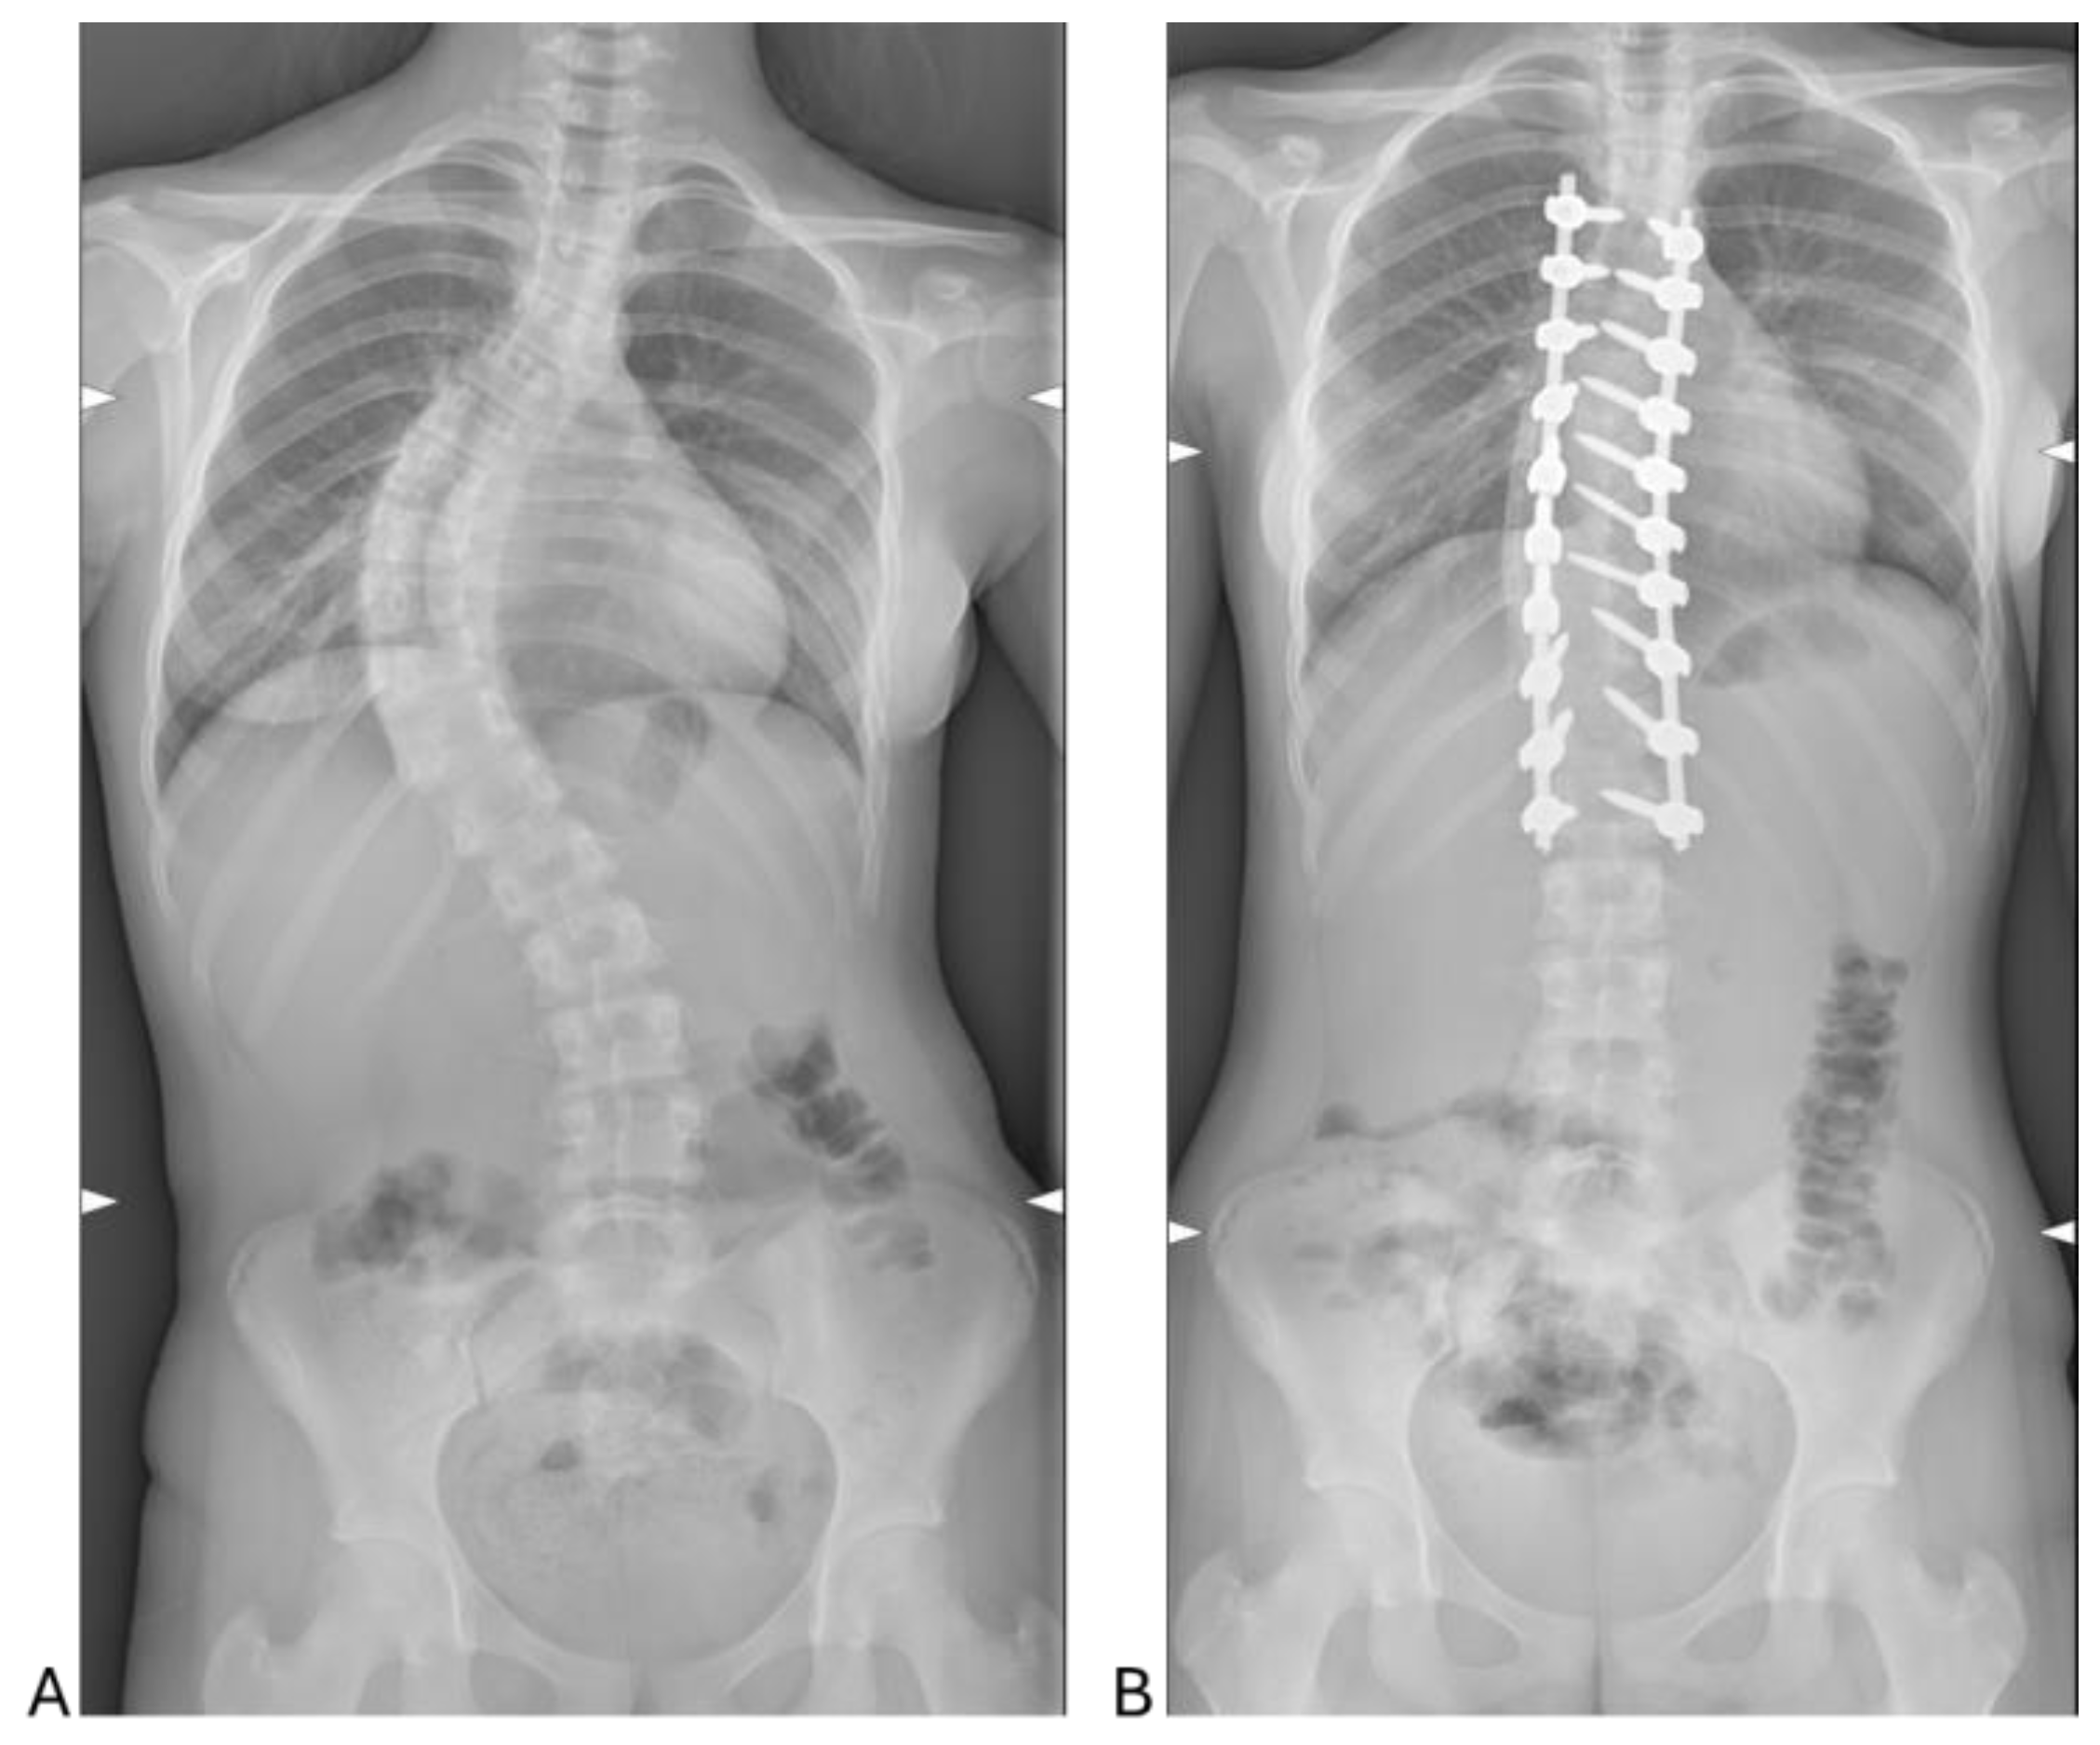

The analysis of radiographic outcomes showed a significant reduction in Cobb angles following surgery (Figure 1). Specifically, the lumbar Cobb angle decreased from 51.78 ± 12.90° preoperatively to 16.50 ± 3.82° postoperatively, reflecting a substantial correction of lumbar curvature. Similarly, the thoracic Cobb angle improved significantly, reducing from 61.82 ± 14.59° preoperatively to 14.33 ± 7.24° postoperatively. These results demonstrate the effectiveness of the surgical intervention in achieving marked corrections of both thoracic and lumbar spinal curvatures.

The patient cohort, comprising predominantly females (26 out of 30), aligns with established epidemiological trends indicating a higher prevalence of AIS in females [16]. The average age of 15.33 ± 1.75 years is consistent with the typical timing for surgical intervention in this condition [17]. The predominance of Lenke Type 1 curves (38.1%) highlights thoracic scoliosis as the most common presentation in AIS, while the sagittal (+) modifier, associated with hyperkyphosis, was observed in 42.9% of cases. This reflects the diverse spinal deformities that characterize AIS, emphasizing the need for tailored surgical and perioperative management approaches [17]. In this context, the study demonstrates the efficacy of PSF in achieving significant radiographic corrections. Postoperative reductions in lumbar and thoracic Cobb angles, from 51.78° and 61.82° preoperatively to 16.50° and 14.33°, respectively, confirm the surgical technique’s ability to restore spinal alignment effectively.

Figure 1. Pre- (A) and postoperative (B) radiographs of representative case with 13-year-old female patient. (A) Preoperative standing Cobb angle of 64° and (B) postoperative standing Cobb angle of 14°.